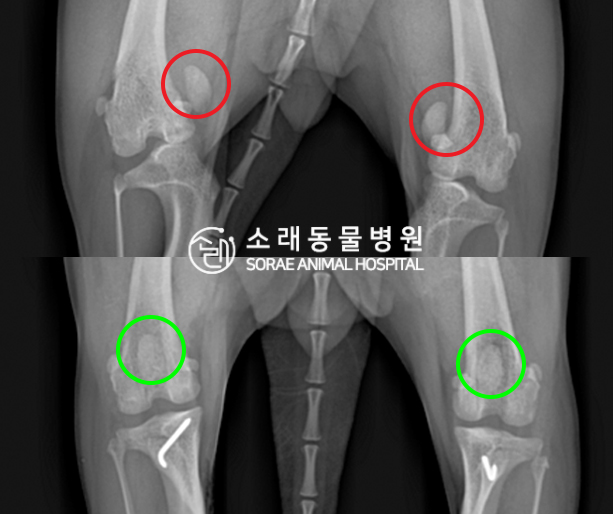

수술전과 수술후에 촬영한 코코의 슬개골

방사선 사진입니다. 나란히 놓고 비교해보니

슬개골의 위치에 확연한 차이가 있는 것을

확인해 볼 수 있는데요. 내측으로 탈구되어 있던

슬개골이 원래 제자리인 활차구에 예쁘게

자리 잡고 있는 모습을 확인할 수 있었습니다.